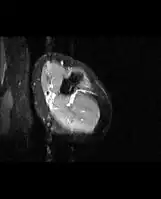

Medical imaging usually shows a well-defined wide-based bony growth on the surface of bone.[5] It can be pedunculated and irregular, giving it a "bizarre" appearance, and is not connected to underlying bone.[2]

MRI mid-arm axial view -